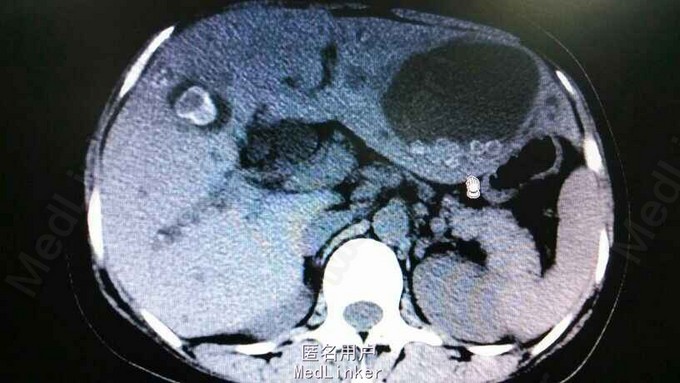

查体:右上腹轻压痛,无反跳痛,余无特殊。辅助检查,肝功,血象正常。腹部CT示肝内多发结石伴胆管囊状扩张。胆总管结石。见图

诊断:肝胆多发结石。治疗:予覆盖敏感菌,利胆等治疗。外科会诊:无法手术,内科治疗为主。